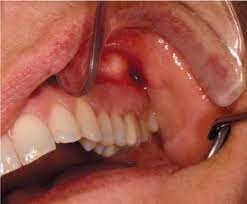

Apical periodontitis refers to the inflammation of the periodontium — the tissue that surrounds your teeth. Apical means "relating to the apex," so inflammation usually occurs around the tip — or apex — of the tooth's root. Two types of apical periodontitis exist:

Typically, apical periodontitis occurs when there's another problem with the tooth. For example, inflammation can develop if a person has an untreated cavity. In some cases, apical periodontitis can develop if the pulp of the tooth becomes infected or dies. Injury or trauma to the tooth can also lead to apical periodontitis.